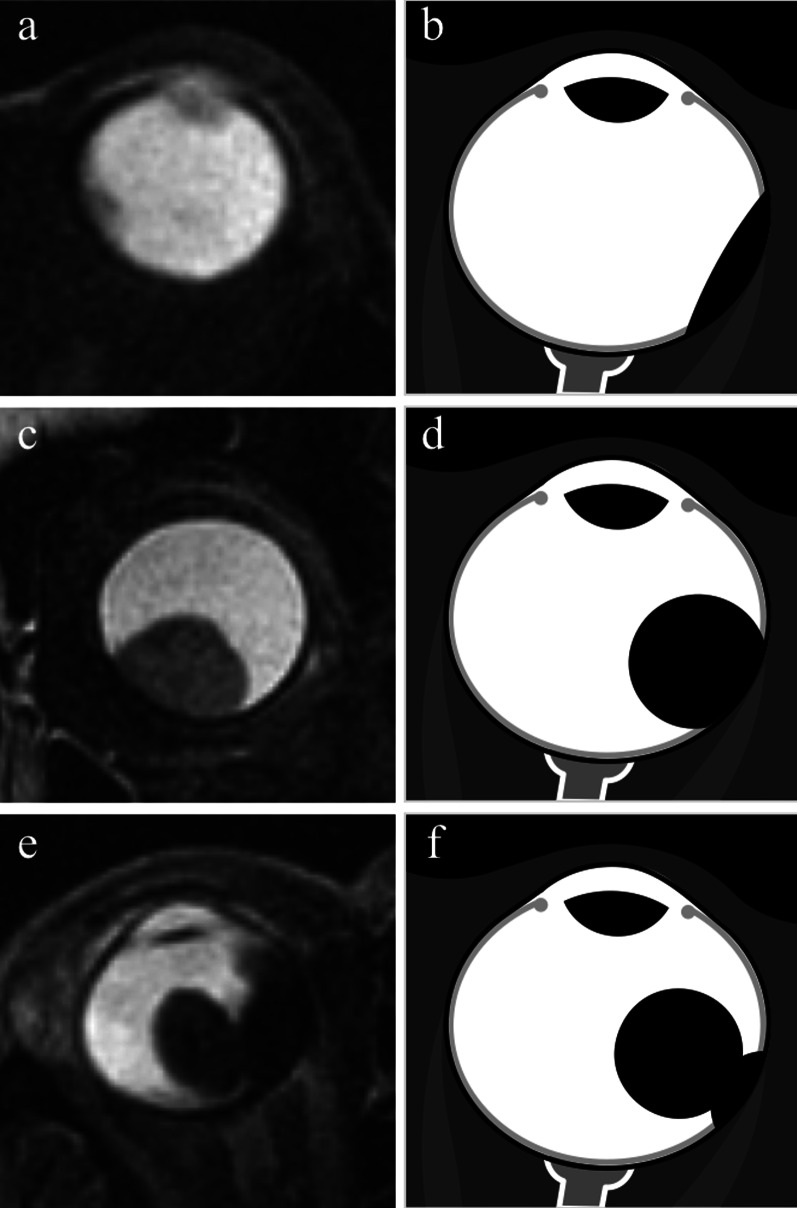

Fig. 11.

Different morphologic features of uveal melanomas. (a, c, e) Axial T2-weighted turbo spin-echo STIR images and (b, d, f) corresponding schematic drawings illustrate the three different macroscopic appearances of uveal melanomas: (a, b) lentiform shape or flat tumor, (c, d) mound or dome shape, (e, f) mushroom or collar-button shape